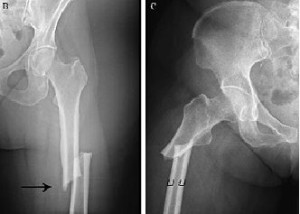

El uso prolongado de bifosfonatos reduce la resistencia a las fracturas

03 agosto 2017

Luego de un uso promedio de 8 años, los bifosfonatos mostraban tejido cortical más mineralizado pero con menor resistencia al inicio y progresión de la fractura femoral. PNAS, 31 de julio de 2017